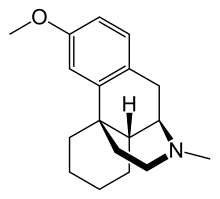

Morphinans

Morphinan series

- Levomethorphan

- Methorphan (racemethorphan)

- N-Methylmorphinan

Structures

| Other morphinans | ||||

Levomethorphan Levomethorphan |

N-Methylmorphinan N-Methylmorphinan |

Dextromethorphan Dextromethorphan  levomethorphan levomethorphan |